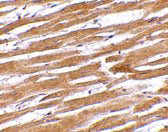

Immunohistochemistry of GPVI in human heart tissue with GPVI antibody at 10 μg/mL.